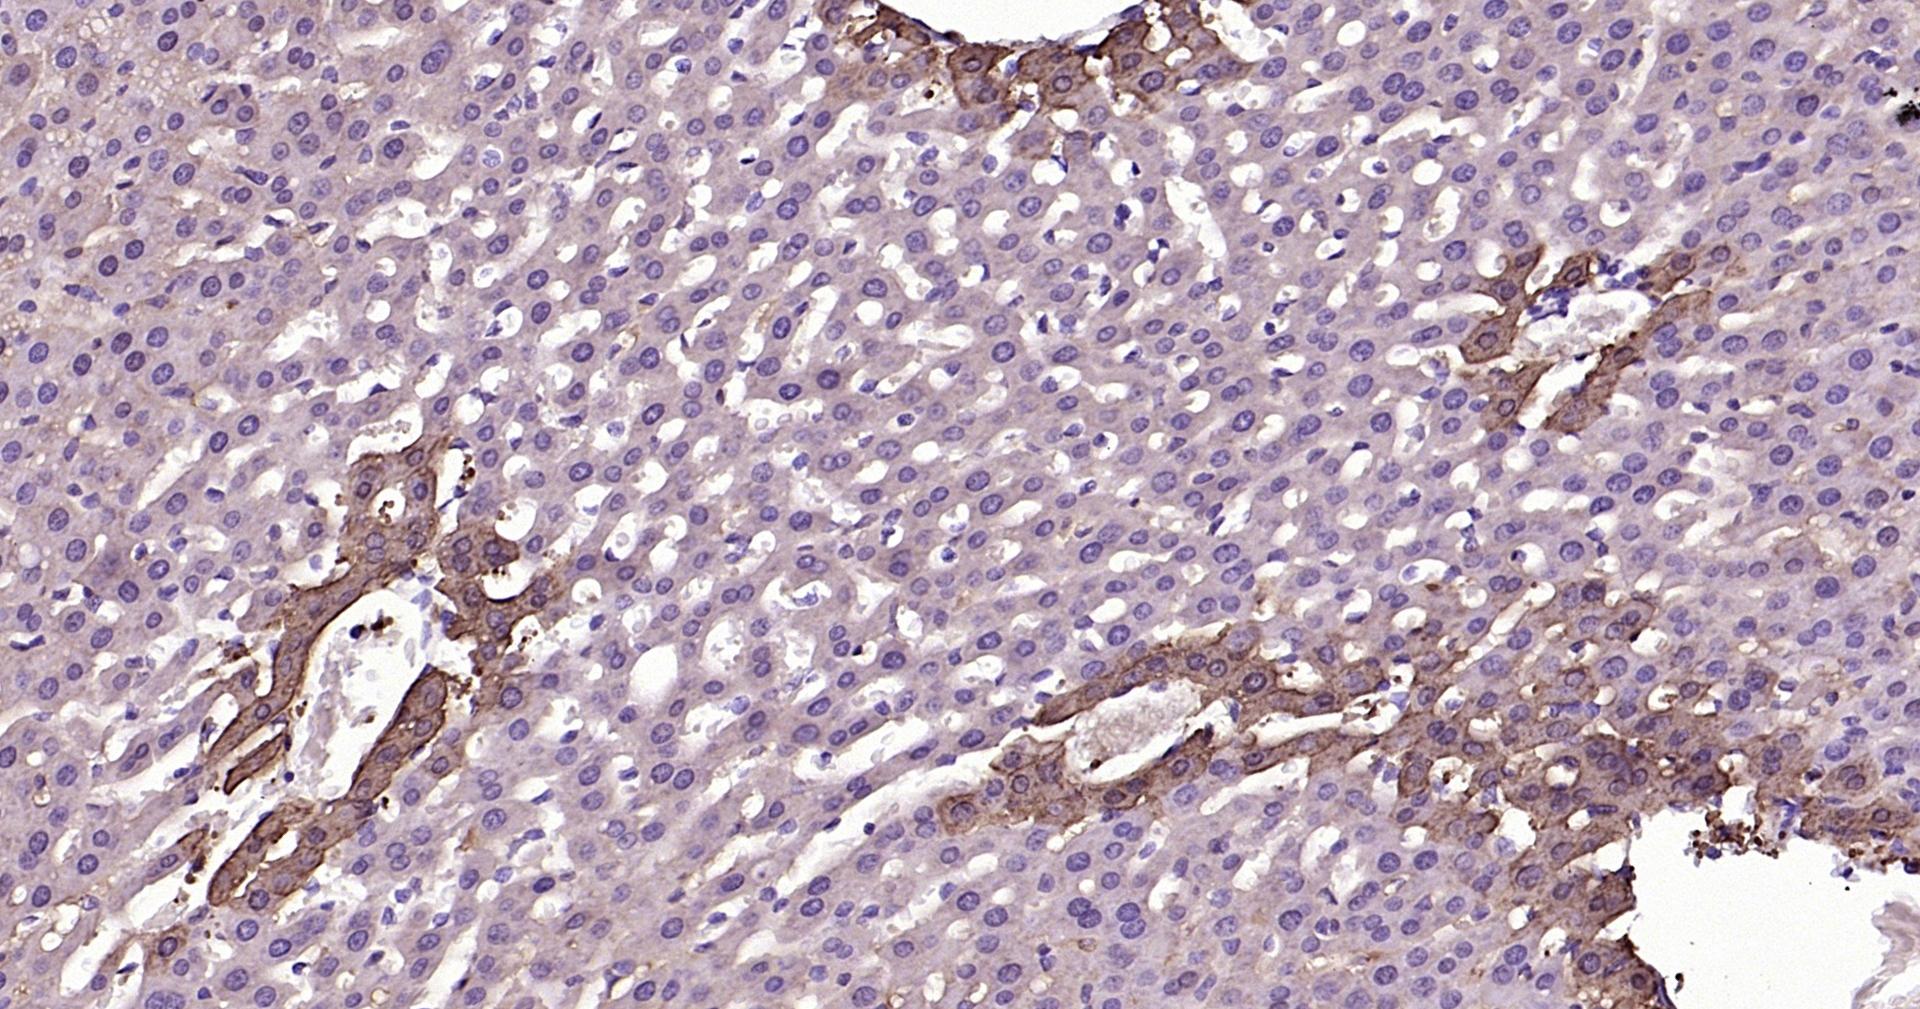

• IHC-P

IHC-P IHC-P1:50-200